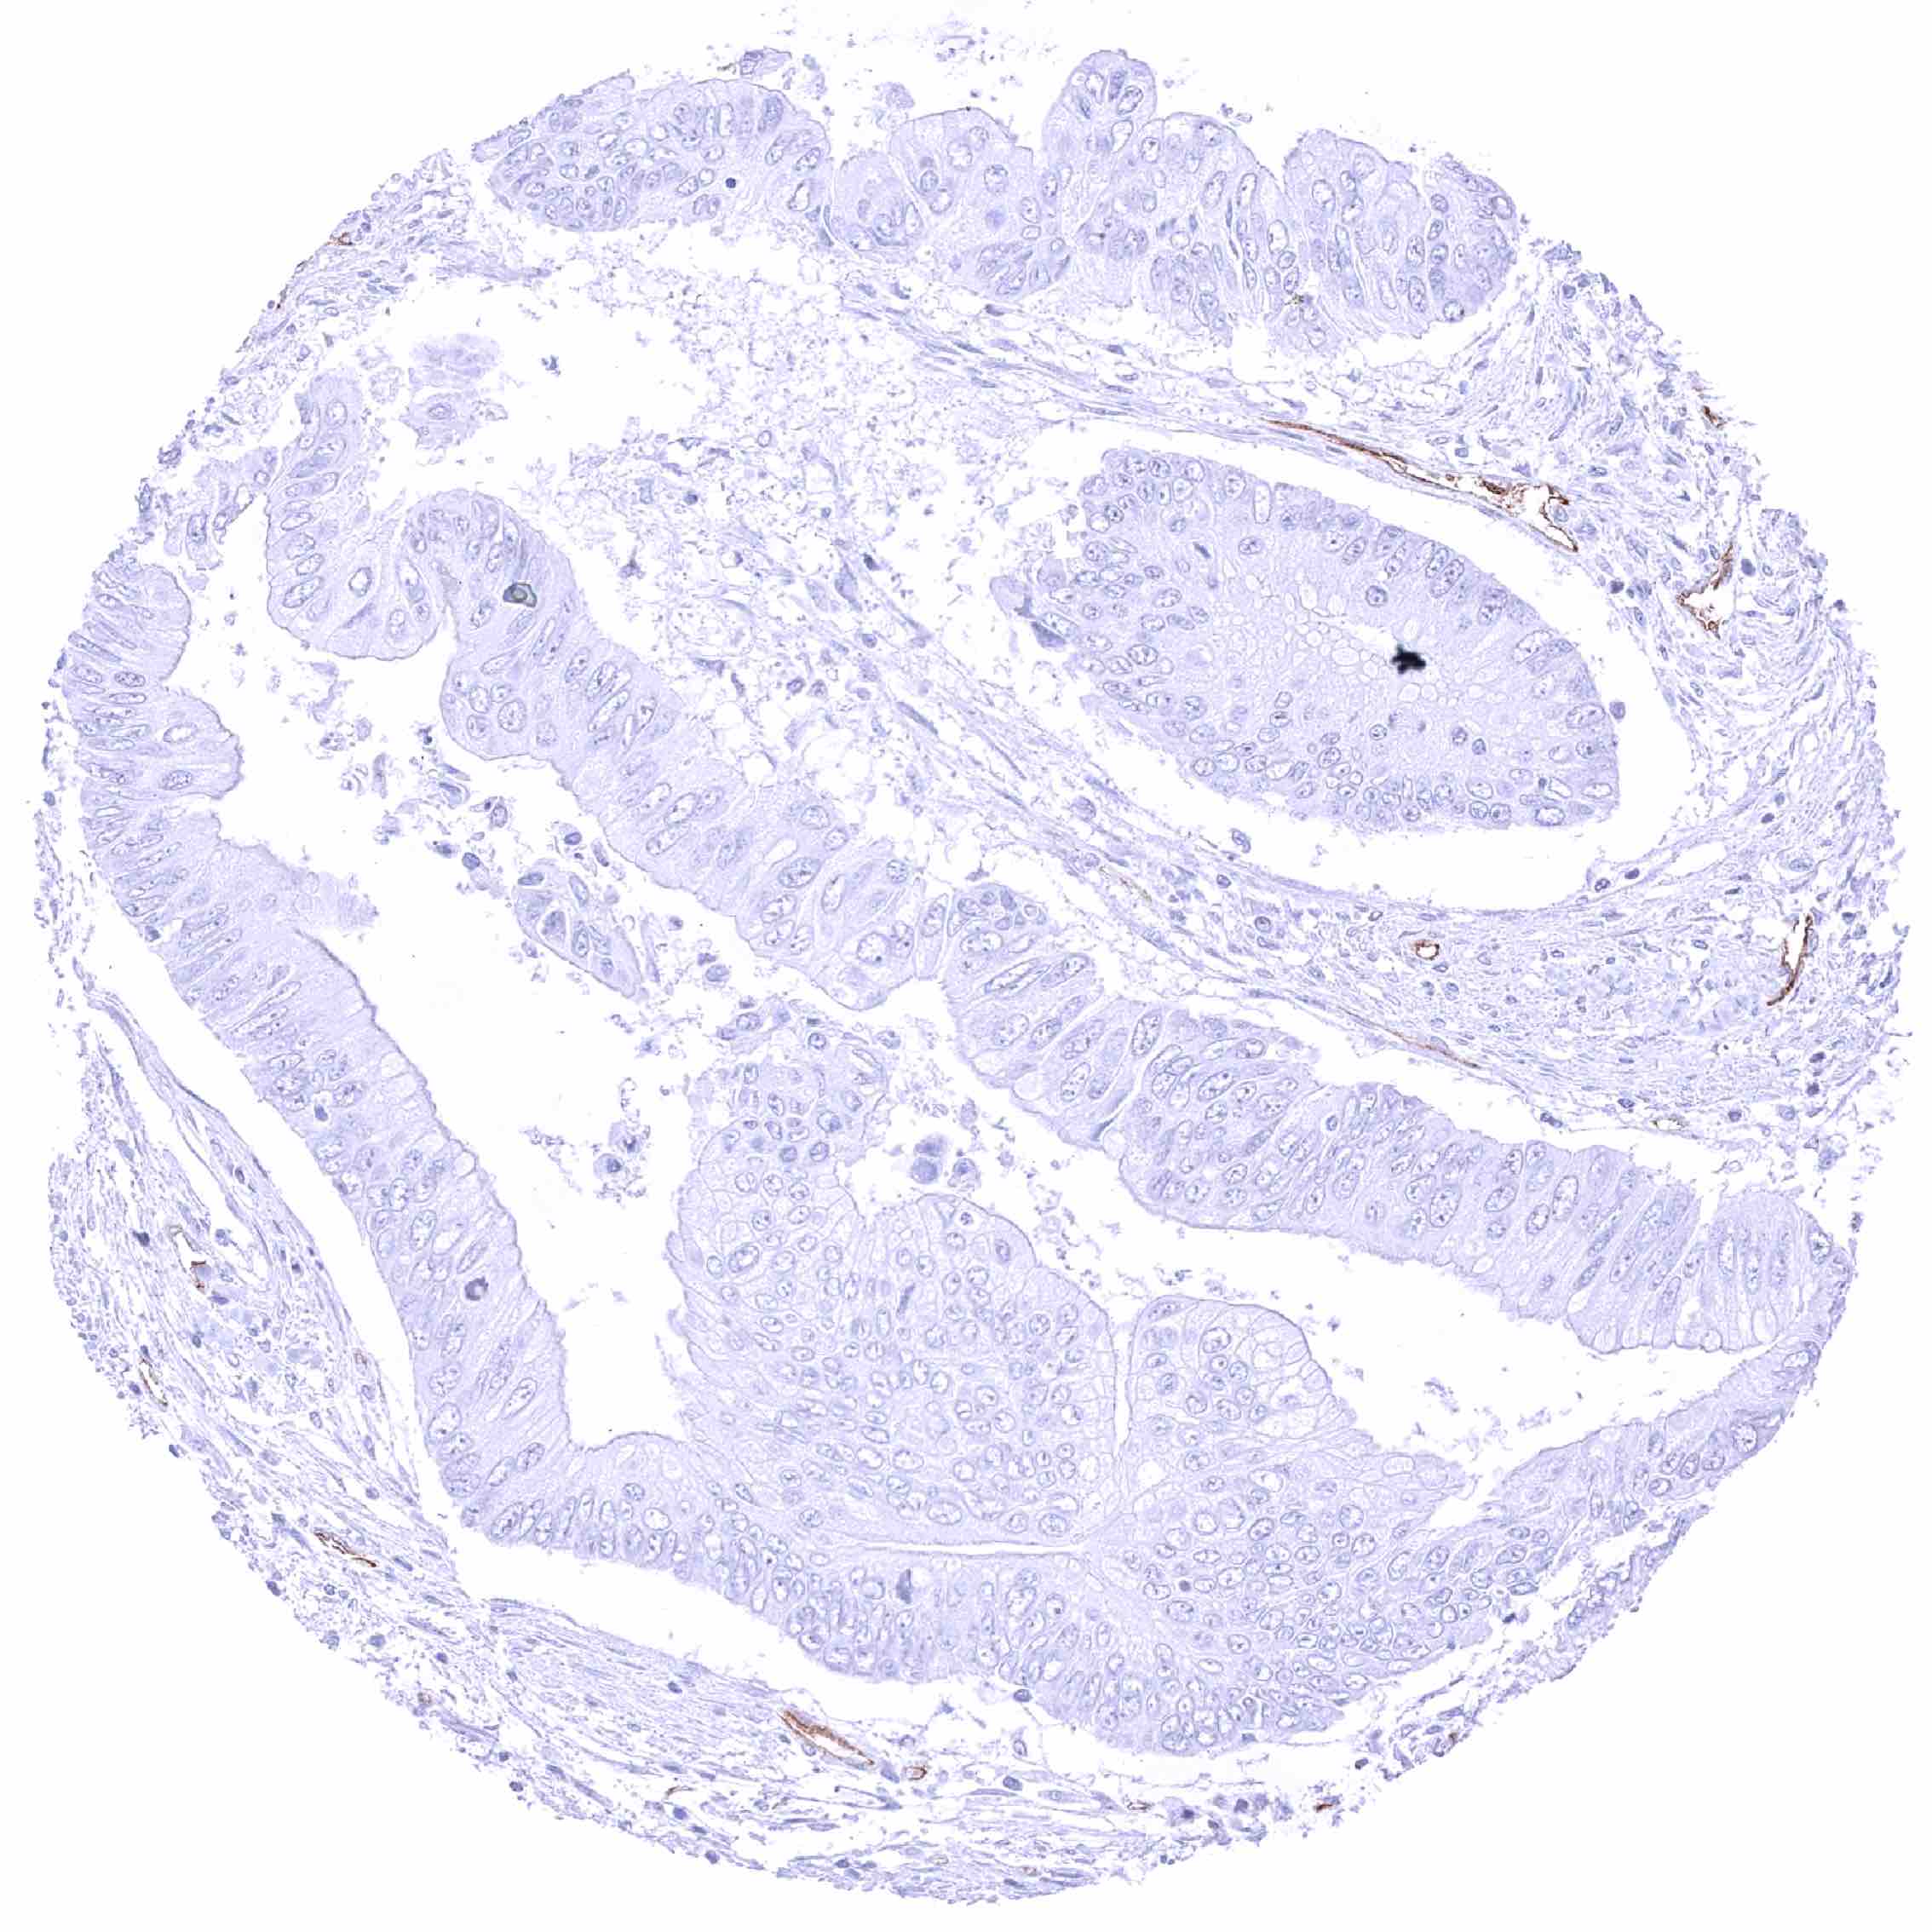

Colon – PODXL negative colorectal adenocarcinoma. .jpeg

Colon – PODXL negative colorectal adenocarcinoma. Distinct PODXL positivity of endothelial cells of tumor associated vasculature.

Colon – PODXL negative colorectal adenocarcinoma. Distinct PODXL positivity of endothelial cells of tumor associated vasculature. (2)